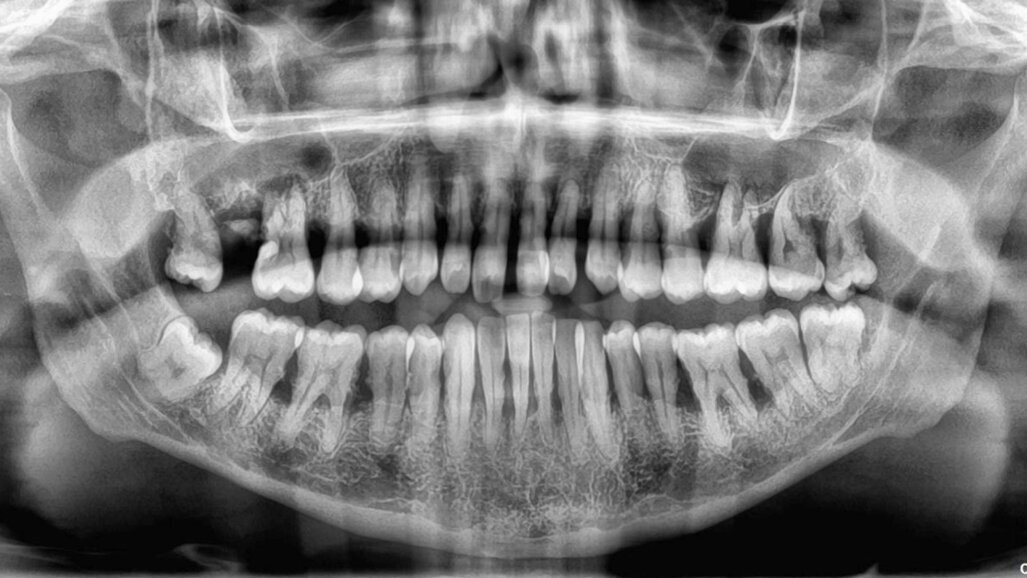

The critical stage of treatment planning is the determination of a tooth’s prognosis. There are several ways of helping with this decision-making – some quite elaborate and expansive taking into consideration both patient factors like willingness and finances and clinical factors like pocket depth, etc.1 Unfortunately, though we make decisions based on bone loss, pocket depth, mobility, etc., —the truth is that the same teeth with the same conditions existing in different patients will have a different prognosis based on hygiene, maintenance, follow-up, masticatory loads, and a certain degree of unpredictability brought in by a wide range of variables that exist at any given time in a patient’s mouth. A clinician’s expertise with regard to both diagnosis and treatment will also determine the success of either treatment. Therefore, following a set flowchart to decide the fate of a tooth is not enough—a clinician needs to bring acumen, experience, something close to intuition, and knowledge of that particular patient to the table. Consolidate all the data and then decide the best course of action.

Even so-called hopeless teeth have been preserved successfully with adequate periodontal treatment followed by strict supportive periodontal treatment (SPT).2,3 Patients with treated aggressive periodontitis have also shown survival of teeth as long as 15 years after treatment.4 This means that patients with seemingly hopeless dentition too could be given the option of holding on to their teeth. They need to be informed that it will just come with a caveat that they must take responsibility for their condition and strictly follow the dentist’s treatment plan and maintenance protocol. At such a time we need to refrain from glamorising the alternative option of an implant—falsely presenting it in a way that suggests that it does not need as much care or that it would last forever. It holds to reason if presented in such a manner 100% of patients who could afford implants, would opt for implants. As soon as an implant is presented as an option it creates a bias in treatment planning as well.5 An implant success rate of 98% and above is misleading as that only refers to its survival in the mouth and not a peri-implant disease, inflammation, or bone loss that afflicts a great number of those surviving implants.6 Therefore, it becomes imperative to present dental implants in a responsible ethical manner—explaining the benefits but also the fact that it is not a fill-it-and-forget-it-situation.

For all patients who opt to save their teeth—the maintenance phase is not just important for the survival of teeth—it is also to ensure no deterioration to a point where it would compromise or jeopardize future implant treatment. We have often in our experience found patients stable for four to six years with regular SPT and suddenly be lost to recall until they turn up ten years later where we are left with no bone to place implants in a conventional manner then resorting to extreme bone augmentation or zygomatic and pterygoid implants. Hence the delicate balance of when saving teeth versus extracting and implants needs to be revisited regularly in each patient to ensure that maintenance of the teeth is not risking the loss of residual bone.